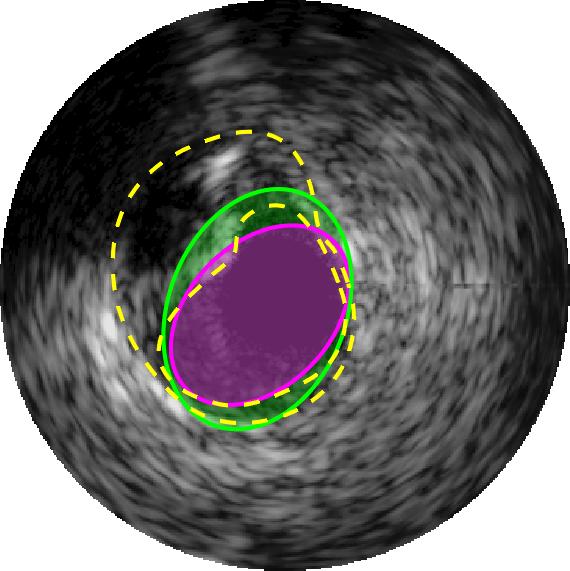

Qualitative evaluations are illustrated in Figure 4 and show the successful segmentation results of the proposed EREL selection strategy for 20 IVUS frames. The lumen areas are highlighted by the magenta colour while the media regions are green. Also, the manually annotated contours for both lumen and media are drawn as yellow dashed lines. As we can see, the chosen frames contain a variety of lumen and media morphologies.

If artifacts that are usually dark (low intensity value) regions, join the lumen and media regions, a type of leak will be created. This leak significantly increases the size and the mean intensity of the regions and generates irregular patterns that are very difficult to distinguish by the EREL extraction algorithm. Some of the inaccurate segmentations that are caused by the presence of the artifacts are shown in Figure 5. As can be seen in Figure 5, although the presence of the artifacts disrupts the detection of the media regions, most of the lumen regions can still be segmented accurately. This is also supported by the quantitative results presented in Table 3. Evidently, even in the presence of artifacts such as bifurcations, side vessels, and shadows, the lumen segmentation performance remains high, though the accuracy of the media segmentation drops. In fact, even in the worst case condition of lumen segmentation that happens when the image contains bifurcation artifacts, the average Hausdorff distance to the gold standard is only mm which is still lower than most of the other methods. On the other hand, the media segmentation is more sensitive to the presence of artifacts. For instance, the Hausdorff metric for media in some cases increases to mm for bifurcation and to mm for shadow artifact. Accordingly, it can be concluded that the lumen segmentation is robust to the common artifacts of the IVUS images.